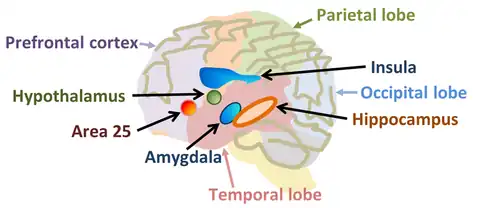

Many schools of psychotherapy see subpersonalities as relatively enduring psychological structures or entities that influence how a person feels, perceives, behaves, and sees him- or herself.[35] According to the hypostatic model, human personality consists of four components or hypostases, which are patterns of behavior related to specific systems in the brain, and are conceptualized by virtually every culture as being characteristic and/or essential to humans:[36][37][38]

- the basic cognitive component – "Homo sapiens" (the intelligent person), which is in connection with sensory areas of the cerebral cortex;

- the verbal subsystem – "Homo Loquens" (the speaking, communicating, and [self-]controlling person), which is connected with the activities of association areas;

- the emotional and motivational subsystem – "Homo Potens" (the powerful and energetic person), which is correlated with the activity of the limbic system;

- the pragmatic (motor) component – "Homo faber" (the productive and industrious person), which is linked to motor cortex activity.